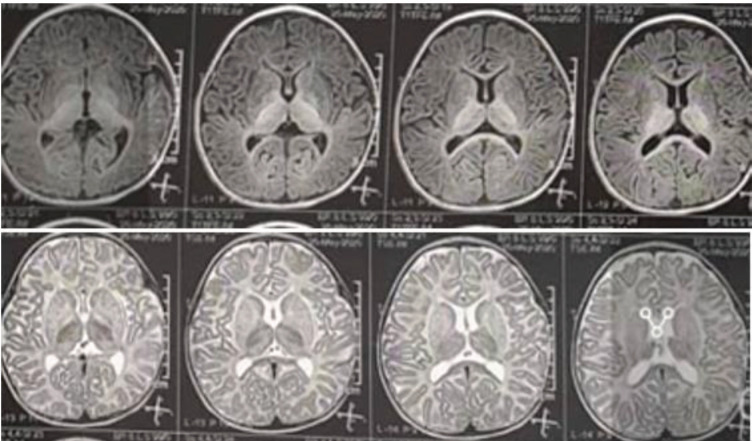

Results: 97.20% of patients were the result of family marriage. Approximately 80% of juvenile patients were developmentally normal before the onset of the disease. Developmental delay was more common among infantile GM1-Gangliosidosis than infantile GM2-Gangliosidosis, but in total, more than 50% of GM1&GM2-Gangliosidosis patients had reached their developmental milestone before the onset of the disease. With the onset of disease symptoms, 100% of patients regressed in terms of movement, 97.20% of them mentally, and 75% of them had seizures during the disease. The most common clinical findings were cherry-red spot, Mongolian spot, macrocephaly, organomegaly, hyperacusis, and scoliosis. The most common brain imaging findings included bilateral thalamus involvement, brain atrophy, PVL, and delayed myelination. The most common finding in electroencephalography was background low voltage with abnormal sharp waves.